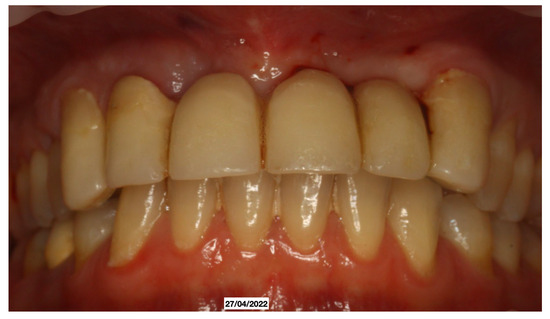

A 52-year-old patient, affected by non-Hodgkin lymphoma since March 2020 and treated with denosumab until June 2021, in clinical remission, presented in January 2022 for observation with multiple root resorptions, not of endodontic origin; it initially affected 22-21-11, but then, with rapid evolution, also affected 23-12-13-14-15-16-17-46-47, without referred pain. The resorption phenomena ended in September 2022. Since then, every radiographic check-up carried out to verify the progress of the regenerative bone surgeries has confirmed the arrest of the progression of the resorption phenomenon affecting the residual dental roots. In February 2022, as soon as responsibility for the patient’s care was assumed, in agreement with the oncology department of the hospital in Bergamo in which he was in care, given the severity of the lesions present (Figure 2), it was decided to extract the teeth (22-21-11), with a surgical toilet of the alveolus associated with decontamination with dye-free laser photodynamic therapy (February 2022).

Figure 2. Evolution of the external resorptions, with a rapid deterioration in only 2 weeks.

It was decided to temporarily rehabilitate the edentulism with a fixed partial denture after preparing 23-12-13 (Figure 4), keeping the adjacent teeth under observation but with a slight radiolucency already present.

Just two weeks later, a rapid worsening was observed (documented with periapical intraoral X-rays) of the elements (13-12-23), which led to their necessary extraction (May 2022), with decontamination of the alveoli, with the beginning of a reabsorption process involving 14-15-16-46-47 (March 2022) with delivery of a removable partial prosthesis (Figure 5).